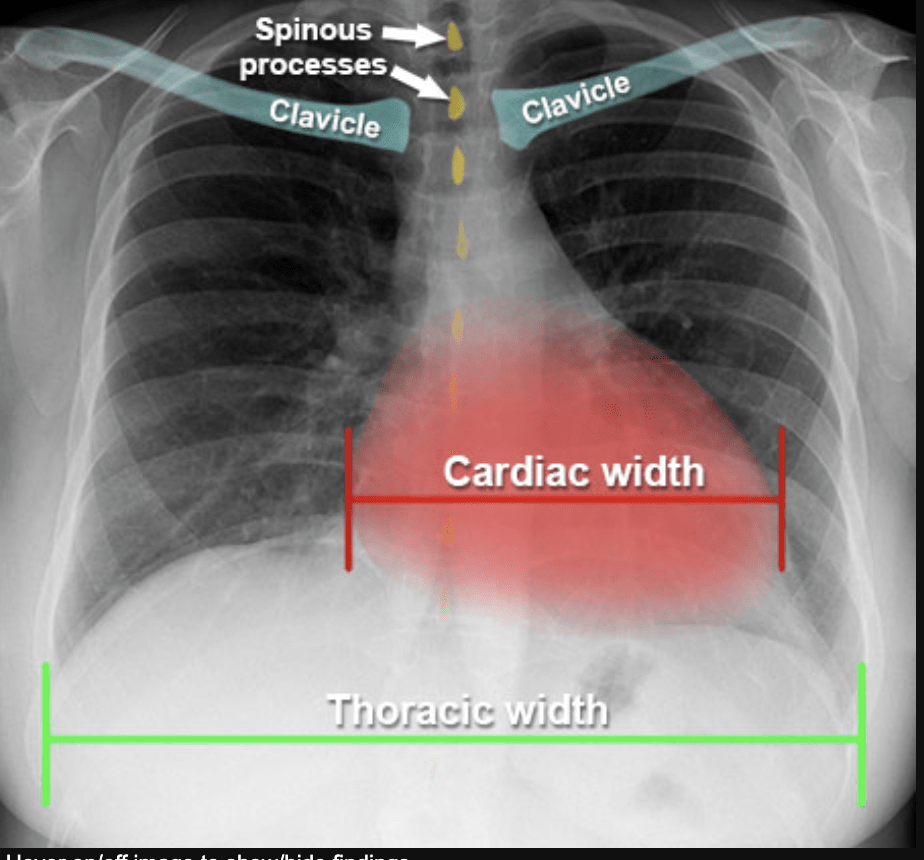

Cardiomegaly - A big heart

What do we look for in a CXR?